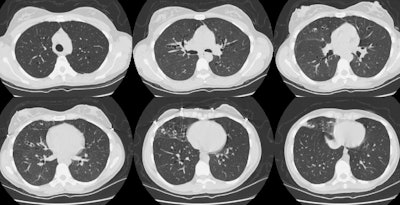

Bronchiectasis:

The patient shown in the CT scan below had a history of a severe respiratory infection for which she did not seek medical attention. The CT scan demonstrates extensive bronchiectatitc changes- more pronounced in the right lung- particularly in the right middle lobe. There is some nodular air space disease in the right middle lobe which may reflect mucous plugging of the distal airways. Other etiologies for extensive bronchiectasis such as cystic fibrosis, dysmotile cilia syndrome, and immunodeficiency syndromes should be excluded. Click here to view zoomed images of the upper and lower lobes.